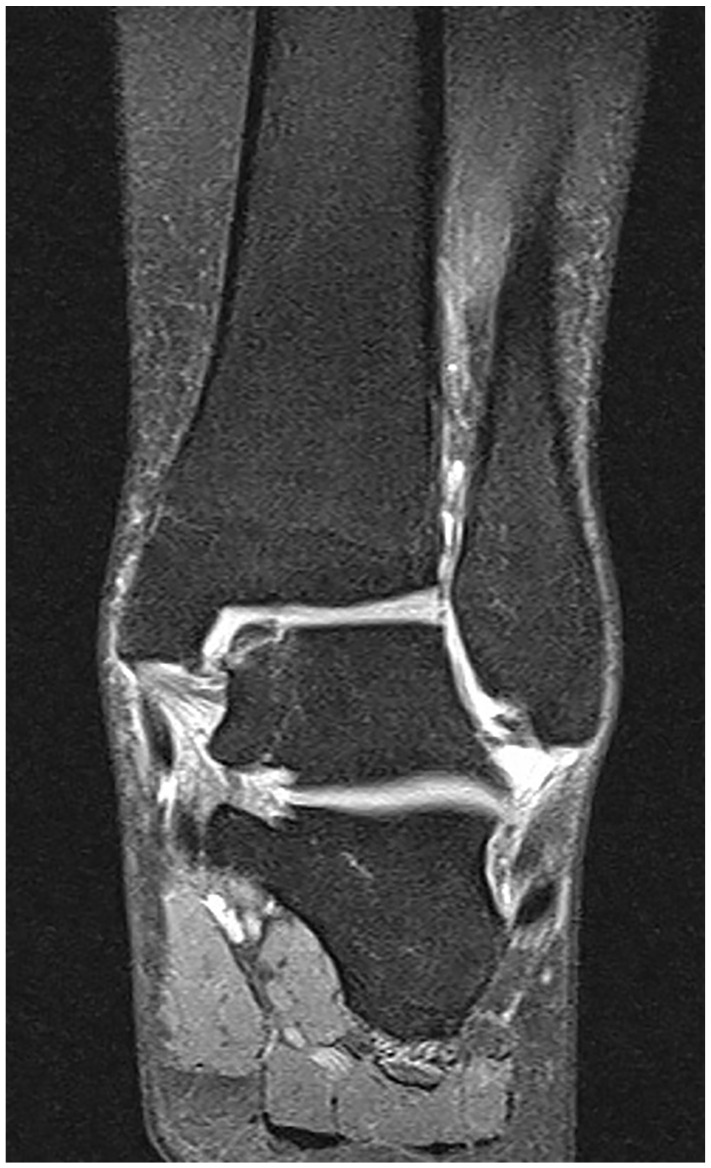

Abstract Image